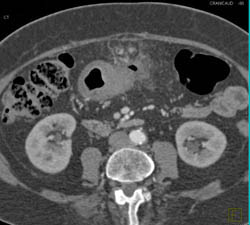

Antral Carcinoma